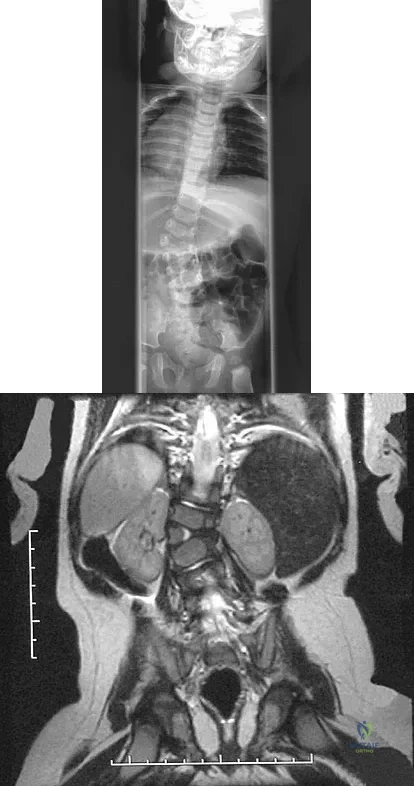

A 13-year-old girl was riding on an all-terrain vehicle when the driver struck a tree. She sustained the injury shown in Figures 45a through 45d. This injury is best described as what type of acetabular fracture pattern?

Correct Answer: Both-column

The fracture is a both-column fracture in the Judet/Letournel classification and a C3 in the AO classification. There is extension into the sacroiliac joint along the pelvic brim and comminution along the posterior column above the sciatic notch. Both the anterior and posterior columns are separately broken and displaced. However, the defining feature of a both-column pattern, as seen in this patient, is that all articular fragments are on fracture fragments and no joint surface is left intact to the axial skeleton above. The use of three-dimensional images makes it easier to view the location of the fracture fragments and the amount and direction of displacement. Helfet DL, Beck M, Gautier E, et al: Surgical techniques for acetabular fractures, in Tile M, Helfet DL, Kellam JF (eds): Fractures of the Pelvis and Acetabulum. Philadelphia, PA, Lippincott Williams & Wilkins, 2003, pp 533-603. Tile M: Describing the injury: Classification of acetabular fractures, in Tile M, Helfet DL, Kellam JF (eds): Fractures of the Pelvis and Acetabulum, ed 3. Philadelphia, PA, Lippincott Williams & Wilkins, 2003, pp 427-475.